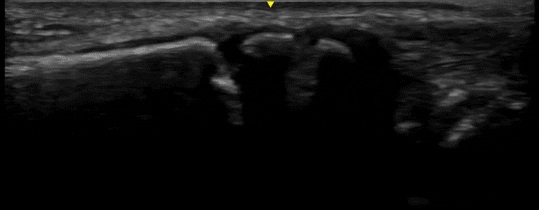

Case 1

Here we see long axis views of the distal radius and ulna in a 12-year-old with a FOOSH injury. The fracture is as plain as day – even the ulnar styloid fracture. In this case, we took the ultrasound machine into the room during the initial evaluation and had these images before we left the bedside.